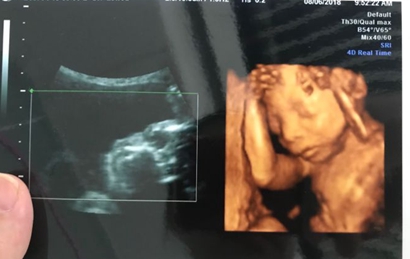

四维彩超最佳时间是在孕24周左右,5个月还未到20周做四维检查的效果并不是很好,目前网上流传的通过四维单子来看男女的方法有如下几种:

一:在彩超单上会印,顶头最右边有两行字,是英文字母和数字组成的,第一行是日期,第二行是时间,如果第一行是M开头,那就是male男,如果是F开头就是female女,第二行打头的T是时间的意思。

二:彩超单上通常有“双侧肾盂分离”,那90%是男孩;如果是“双侧肾盂未见明显分离”,那95%是女孩。

三:彩超单上很小英文字母Qual high 1是女孩,2是男孩。

四:通过四维彩超图看清胎儿性别,在六个月以后照四维彩超,只要宝宝的姿势是正面不是给个背影什么的,是男是女一看就知道。不过因为国家明文规定不能查胎儿性别,所以医生不会把能明显看出性别的一面照给妈妈看。